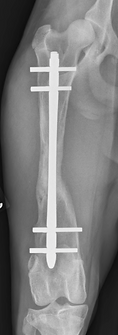

Fractures can be treated using a variety of methods, depending on severity, location, and patient factors. Options include:

Surgical repair may use plates and screws, rods or nails, or external fixators. Decisions depend on location, configuration, displacement, soft tissue condition, patient age, and underlying bone health. Prompt treatment is preferred, though life-threatening injuries always take priority. Postoperative care is critical to prevent implant failure and ensure healing.